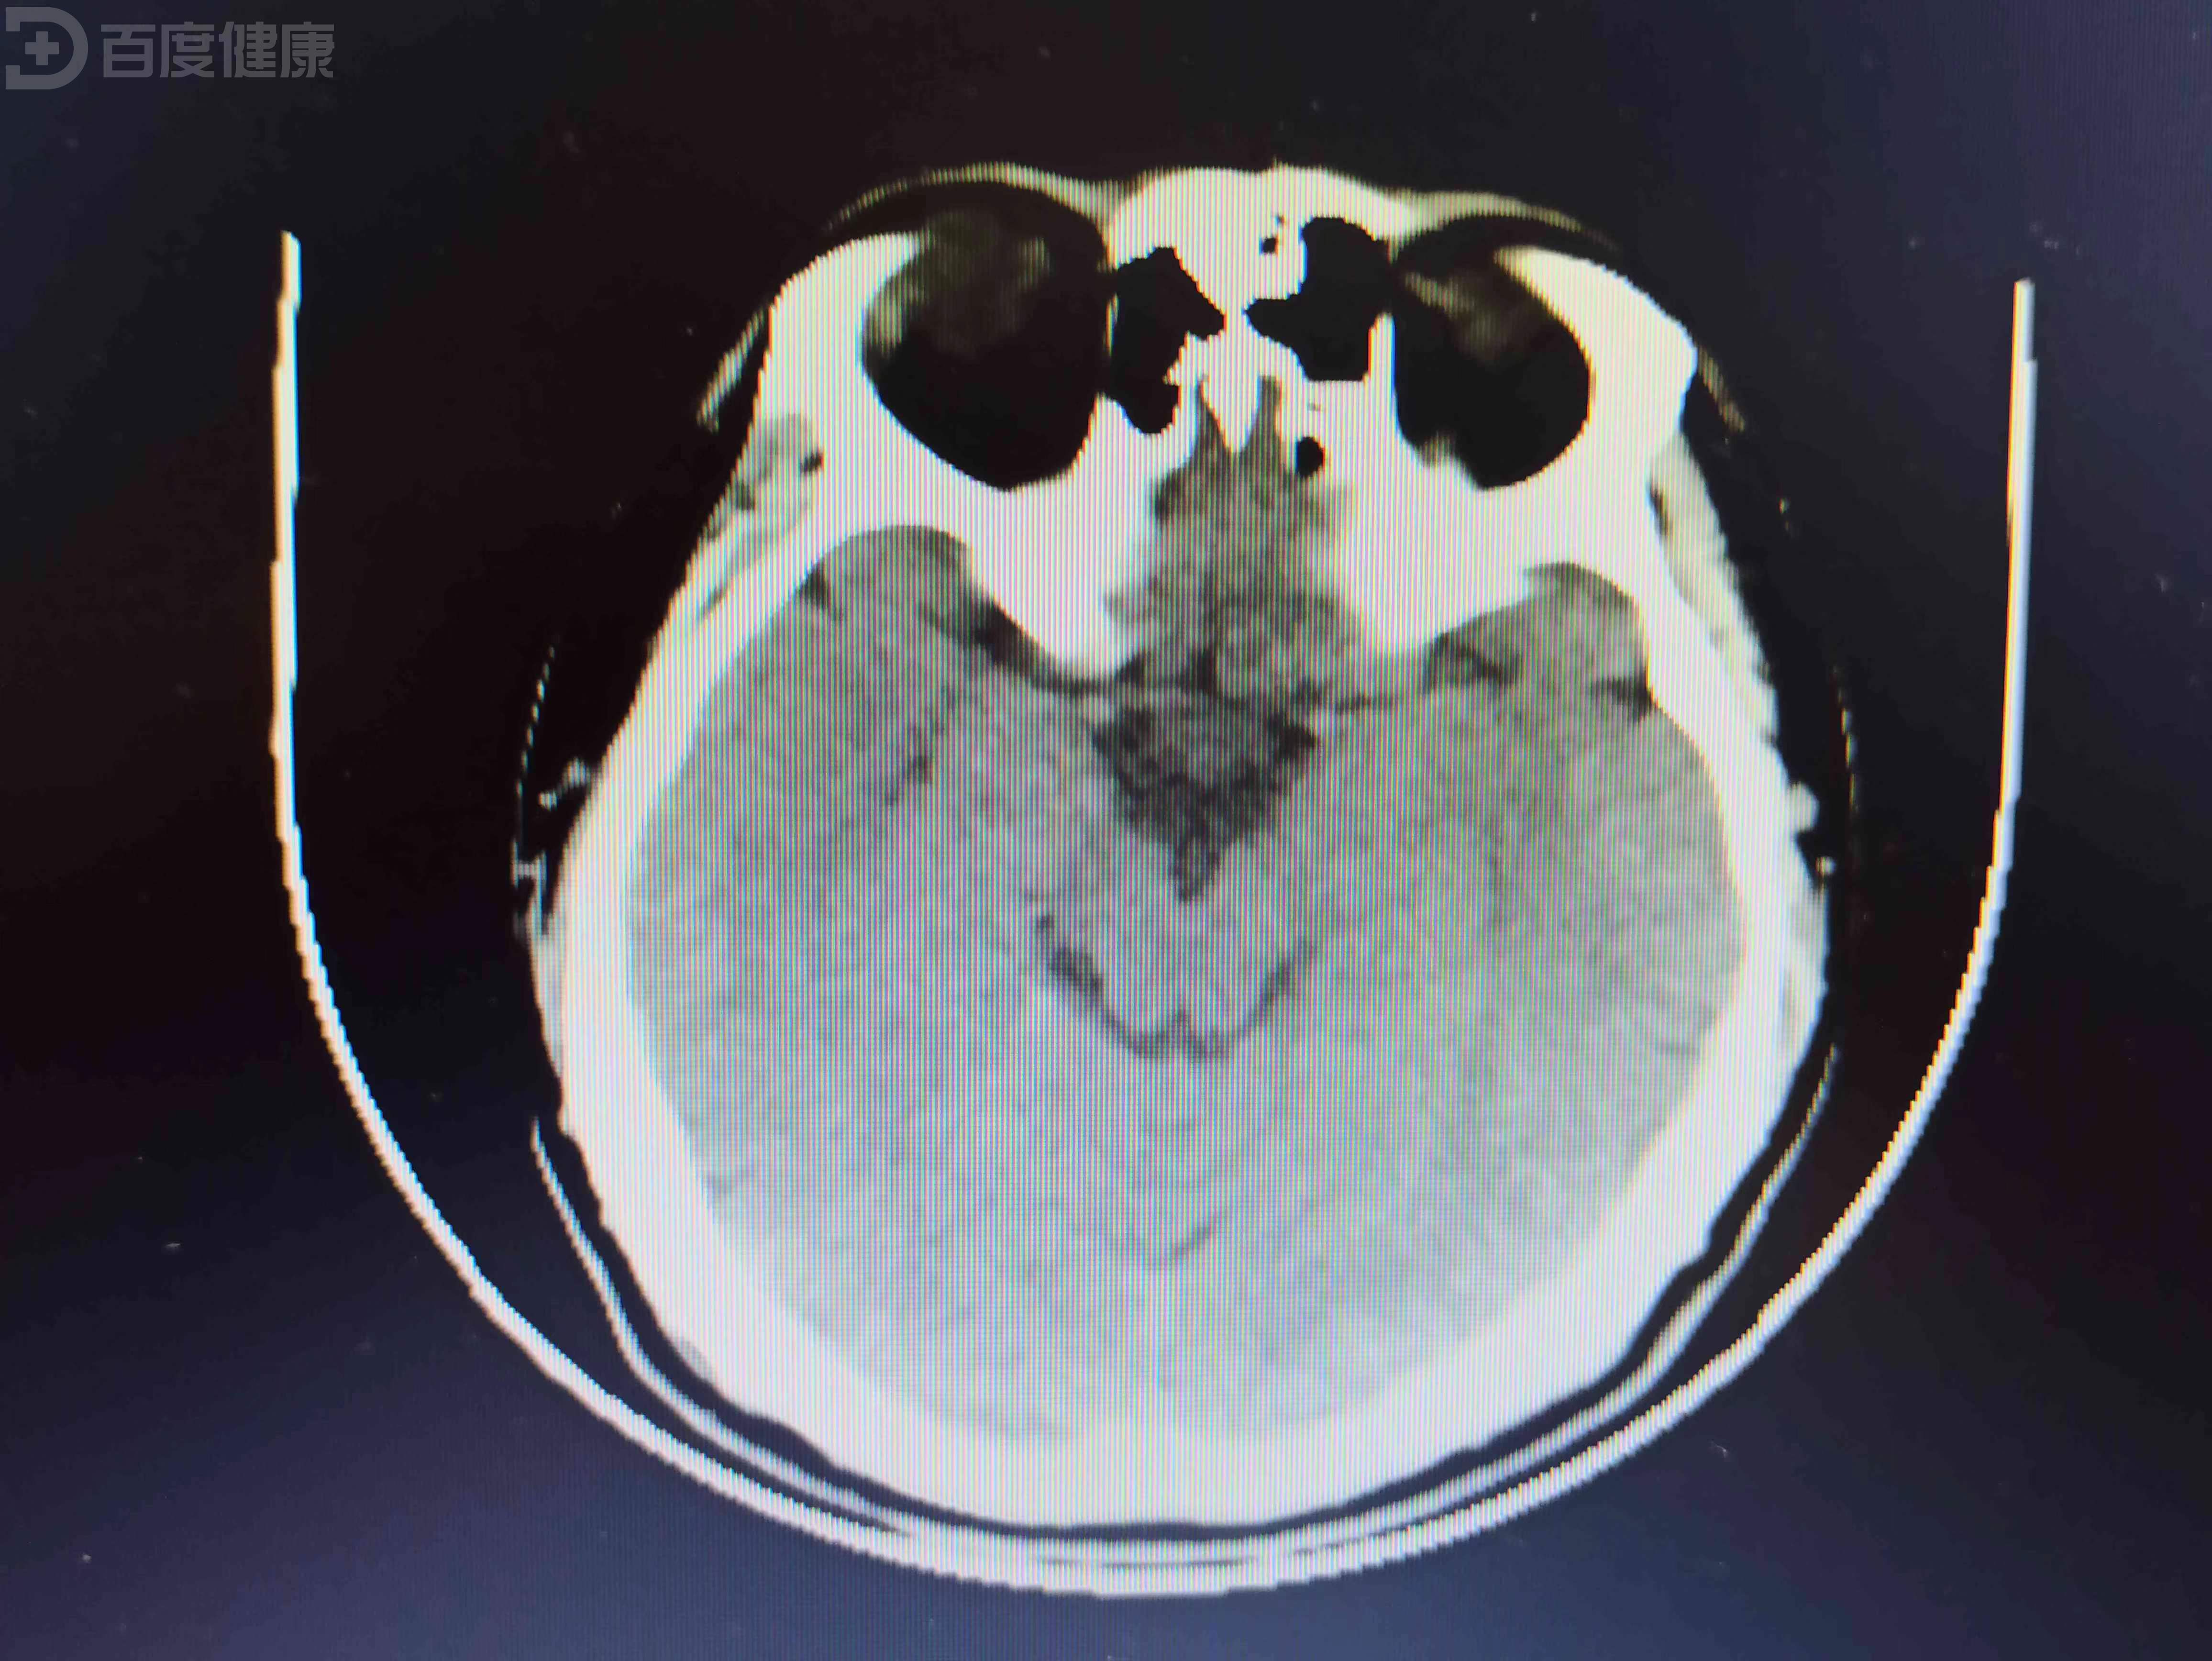

他临时抽调两名经理进修学习,自己则代为效劳。距上次那通电话已过去三月有余,在此期间,迟烨再没有联络过周御璋,周御璋也不愿无故打搅迟烨生活,因而只要求助理密切关注医院方面动向。老话讲,由奢入俭难,更何况是天翻地覆的巨变,/视/察/前,周御璋设想过迟烨的状态难免消沉。集团总裁亲自视察,领导召集全体员工等候讲话,周御璋有心留意,一眼就发现站在人群中的迟烨。 迟烨身穿工作服,头戴安全帽,出乎意料,他的脸色和精神都恢复得不错。午休,周御璋到工厂食堂用餐,他远远望见迟烨与同事边打饭边聊天,用完午饭,周御璋/视/察/各部门,他走至库房区域看见迟烨站在厢式货车内拆卸集装箱。迟烨的袖管挽到肘部,他明显黑了瘦了,但脸上始终带着明媚的笑。下午,周御璋还另有行程,分工厂领导去为他叫司机,周御璋低头处理工作信息,他听到脚步声,迟烨急匆匆朝他跑过来。迟烨从工作服口袋里掏出盒热牛奶,周御璋勾唇笑了笑,迟烨怯怯地把热牛奶递向他。周御璋推了下鼻梁上的镜架,问迟烨工作累不累,迟烨涨红脸答,不累不累,谢谢您。这天过去,周御璋再见迟烨已是半月后,地点还是医院。事情的原委很简单,分工厂库房屡屡失窃,造成/经/济/损/失/,迟烨为捉到内贼将排班调到傍晚,内贼果真故技重施,迟烨决定抓现行,可谁知内贼随身携带木质棒球棍。迟烨头部受伤,中度脑震荡,周御璋守在病房外,他派助理负责照料。病房饮水机里是开水,迟烨脚步虚浮,动作迟缓,双手端不稳瓷杯,病房门嵌块窄玻璃,助理尚未作出反应,周御璋寒着脸破门而入。迟烨彻底愣住,周御璋将瓷杯放去旁边,不由分说,拦腰把迟烨横抱回病床。